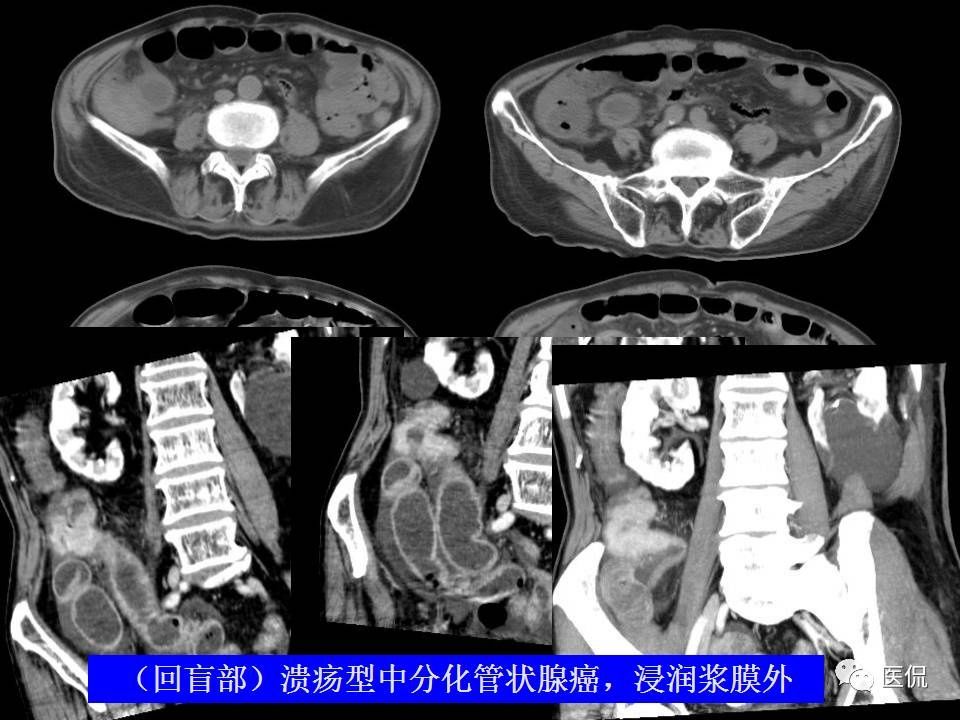

急性阑尾炎的CT诊断及鉴别诊断

960x720 - 45KB - JPEG

960x720 - 75KB - JPEG

960x720 - 52KB - JPEG

960x720 - 56KB - JPEG

960x720 - 49KB - JPEG